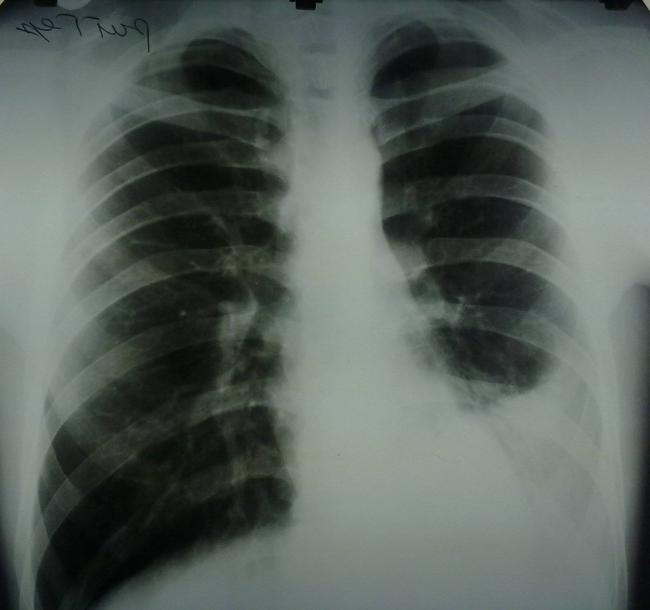

Помимо опроса и объективного осмотра, включающего перкуссию и аускультацию грудной клетки, проводят рентгенологическое исследование в двух положениях тела (в 2-х проекциях). Это основной метод обнаружения ателектазов легких.

На рентгеновских снимках выявляют следующие признаки, указывающие на спадение легочной ткани:

Однородное затемнение в области поражения. Размеры тени зависят от вида ателектаза: при долевом выявляется обширное затемнение, при сегментарном — в виде клина или треугольника, расположенного вершиной к корню легкого, дольковые ателектазы множественные и похожи на очаговую пневмонию. Дистензионный ателектаз расположен низко, около диафрагмы, имеет небольшие размеры и вид поперечных полос или темных дисков. Смещение органов: при компрессионном ателектазе смещение наблюдается в здоровую сторону, так как на стороне поражения давление больше, при обтурационном, наоборот – смещение будет в сторону ателектаза, так как на стороне поражения нарастает притягивающее отрицательное давление. Подъем купола диафрагмы – это видно по расположению печени.

Помимо всего перечисленного выше, рентгеноскопия, то есть исследование «вживую», позволяет увидеть куда смещаются органы в зависимости от фазы дыхания, кашля. Это является дополнительным признаком ателектаза, помогающим выявить тип болезни.

Во время инструментальных диагностических манипуляций важно не только установить наличие ателектаза и его точную локализацию, но и уточнить объем спавшейся ткани, чтобы определить правильную тактику лечения и объем лечебных манипуляций. На рентгенограмме для диагностики ателектаза имеет значение состояние не только ткани легких, но и корней легких, ребер, органов средостения, купола диафрагмы, плевры, плевральной полости и даже позвоночника (будет наблюдаться его сколиотическое отклонение в направлении выпуклости в сторону пораженного легкого)

На рентгенограмме для диагностики ателектаза имеет значение состояние не только ткани легких, но и корней легких, ребер, органов средостения, купола диафрагмы, плевры, плевральной полости и даже позвоночника (будет наблюдаться его сколиотическое отклонение в направлении выпуклости в сторону пораженного легкого).